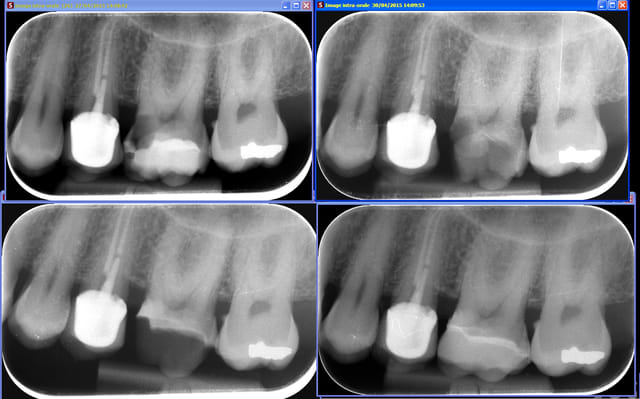

Ma petite contribution :

Reprise carieuse sous composite, juxta-pulpaire, cavité très profonde en mésial.

Eviction carieuse, Biodentine, remontée de marge, IDS et onlay Emax

C'est surtout pour la gestion de la proximité pulpaire et la remontée de marge que je poste, je n'ai pas la photo de l'onlay de toute façon il était pas très esthétique (Emax Cerec, pas eu le temps de retravailler les sillons ni de maquiller).

J'essaierai de faire des photos de chaque étape de la remontée de marge la prochaine fois (et de l'onlay lol).